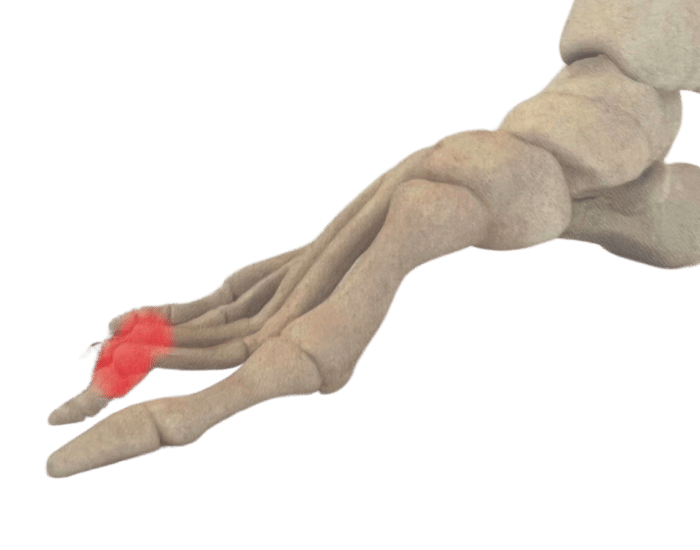

There are numerous reasons why you might need Custom Foot Orthotics. If you have pain in your foot, heel, knee or hip, have high arches or flat feet; or just being regularly on your feet and are getting any aches or pains in the feet or legs, or suffering from general foot pain while walking, running, playing sports or even at rest you qualify for Custom Foot Orthotics.